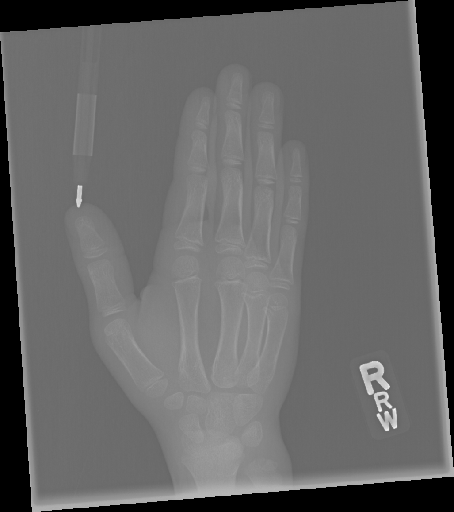

In this work, we focus on a subset of the MURA dataset [17] containing only hand images. In total, we have 5,543 images of 2,018 studies of 1,945 patients. Each study is labeled as negative or positive, where positive means that there was an anomaly diagnosed in this study. There are 521 positive studies, with a total of 1,484 images. Figure 1 shows some examples from the dataset. In summary, our contributions are as follows:

In addition to the numerical results we also showcase some qualitative results. For all methods with reconstruction loss, i.e. all AE as well as -GAN, we can generate heatmaps visualizing the pixel-wise losses. Thereby, we can highlight regions that could not be reconstructed well. Following our assumption, these regions should be the anomalous regions. In Figure 5, we can see prototypical examples produced by CAE. The upper image shows a hand contained in a study which was labeled as normal. We can see that the reconstruction error does not occur concentrated, but is rather spread widely across the hand. The maxima seem to occur around joints, which due to their more complex structure are likely to be harder to reconstruct. Compared to the lower image, which shows a study labeled as abnormal, we see a clear highlighting at the middle finger. Visible also for a non-expert, we can spot metal parts in the X-ray image at the very same location. For those anomalies which could be validated by a person without a medical background, the highlighted regions seem to correspond largely to those anomalous regions.